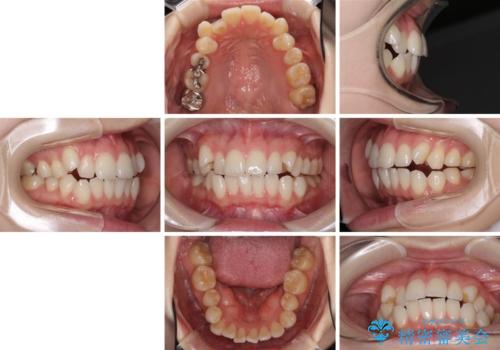

- 前歯のデコボコや八重歯の様になっていることを気にして来院された患者様です。

犬歯捻れて前方に飛び出しており、下顎前歯もそれに沿うようにデコボコとなっていました。

IPR(歯と歯の間を削る処置)によりスペースを獲得して上下顎前歯のデコボコを改善し、前歯が前方に突出しないように設定した上で、インビザラインにて矯正治療を行うこととしました。

途中体調を崩され、長い期間矯正治療を休むことになったため4年半ほどの治療期間がかかりました。